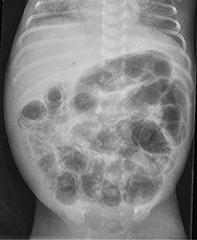

• als verpleegkundig specialist welke radiologische bevindingen er kunnen ontstaan bij NEC en hoe deze te onderscheiden zijn